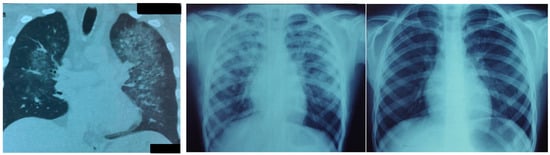

The Failure of Pulmonary Oxygen Exchange in Severe Viral Lung Disease: Pneumolysis

by Gustavo Zubieta-Calleja, Felipe de Jesús Montelongo, Manuel Gabriel Romo Sanchez, Michele Samaja and Natalia Zubieta-DeUrioste

Oxygen 2026, 6(2), 7; https://doi.org/10.3390/oxygen6020007 - 27 Mar 2026

Background: Severe lung compromise from COVID-19, ARDS, and recently AH3N2 can progress to life-threatening hypoxia. Past experience led to standardized protocols that assumed similarity to SARS-CoV. Methods: COVID-19 pathophysiology and histopathological lung biopsy photomicrographs are analyzed. Results: Pneumolysis is defined [...] Read more.

Background: Severe lung compromise from COVID-19, ARDS, and recently AH3N2 can progress to life-threatening hypoxia. Past experience led to standardized protocols that assumed similarity to SARS-CoV. Methods: COVID-19 pathophysiology and histopathological lung biopsy photomicrographs are analyzed. Results: Pneumolysis is defined as progressive alveolar–capillary destruction resulting from SARS-CoV-2 attack on pneumocytes. In the final stages preceding pneumolysis, molecular mechanisms in the lungs include apoptosis in alveolar epithelial type I and II cells, compromising alveolar regeneration, and necrosis, resulting in leakage of intracellular contents and amplifying inflammation. Pyroptosis, driven by inflammasome activity, further disrupts alveolar integrity in ARDS. Histopathological findings include Masson bodies, alveolar-coating cells with nuclear atypia, reactive pneumocytes and reparative fibrosis, intra-alveolar hemorrhage, moderate inflammatory infiltrates and abscesses, microthrombi, hyaline membrane remnants, and emphysema. The three theoretical pathophysiological stages of progressive hypoxemia (silent hypoxemia, gasping, and death zone) are shown. Conclusions: Silent hypoxemia rapidly progresses to critical hypoxemia. This progression results from progressive pneumolysis, inflammation, immune overexpression, autoimmunity, and HAPE-type edema, leading to acute pulmonary insufficiency. Long-lasting COVID-19 can result in fibrosis and, as a compensatory mechanism, polierythrocythemia. The proposed treatment (based on tolerance to hypoxia and the hemoglobin factor) includes prompt oxygen administration, control of inflammatory and immune responses, antibiotics, rehydration, erythropoietin and platelet aggregation inhibitors. Full article

Show Figures

Graphical abstract